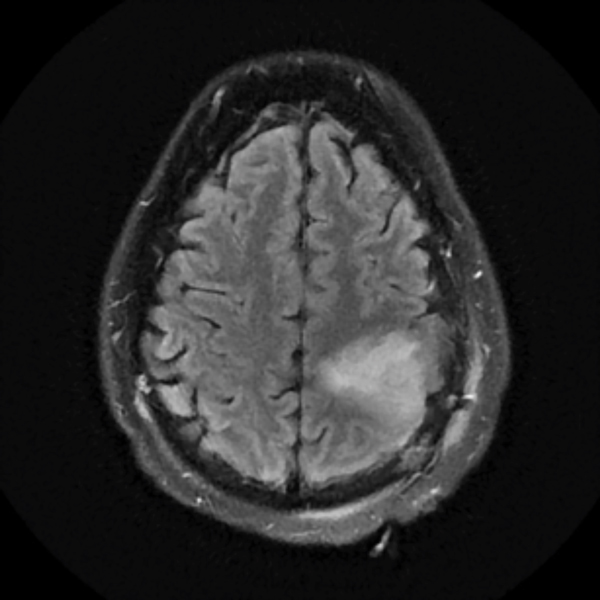

December 2019

Treatment with chemotherapy and radiation under the care of Dr. Grewal resulted in a durable response of the tumor as evident in the post-treatment images.

The patient has returned to work with a resolution of cognitive impairment, has no neurological impairment, and the tumor continues to shrink on each serial MRI.